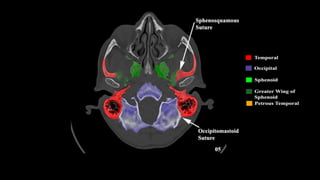

Pseudo-fractures

Extrinsic Fissures &

Sutures